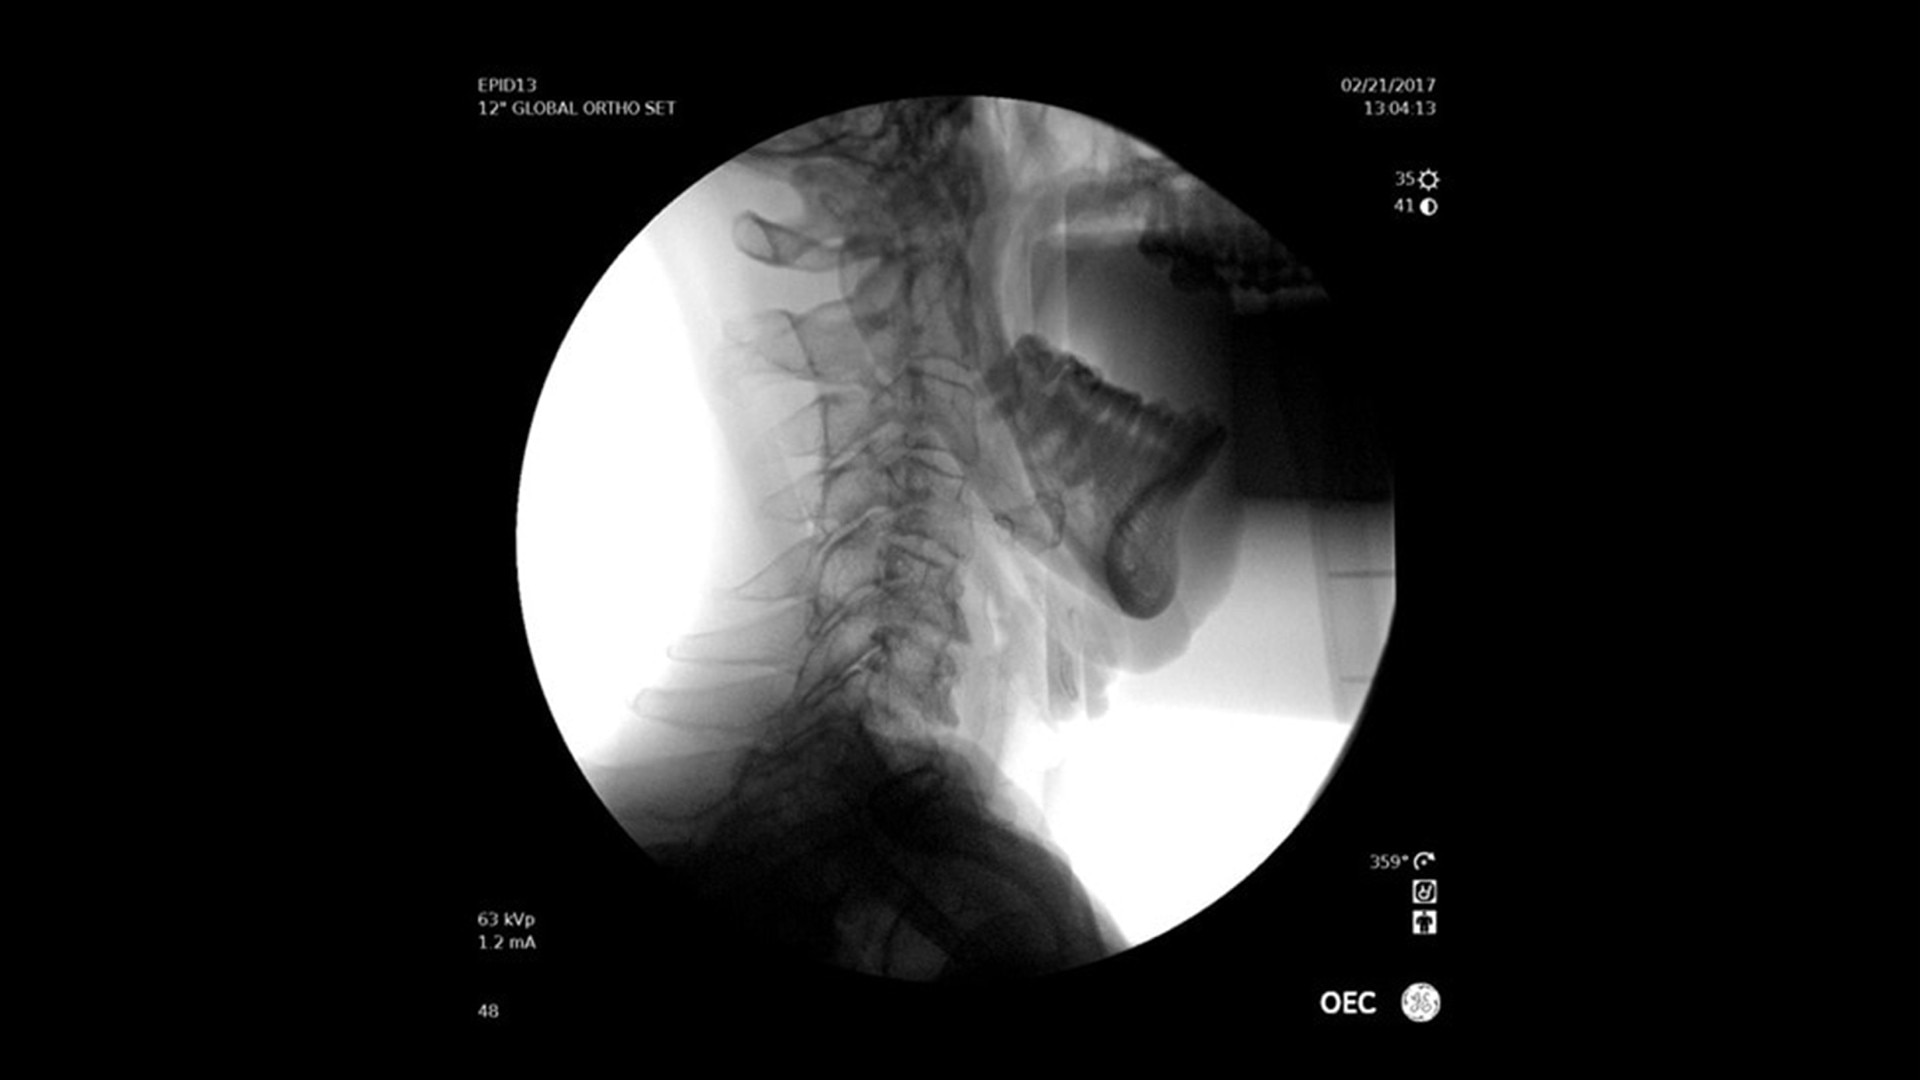

Vielseitig einsetzbar – ideal für orthopädische, gastrointestinale, endoskopische, urologische, neurologische und vaskuläre Eingriffe sowie für die Intensiv- und Notfallmedizin.

Der OEC Elite unterstützt Ihr OP-Team mit fortschrittlicher Bildverarbeitung, die sich dynamisch an klinische Anforderungen anpasst. So entstehen jederzeit präzise und detailreiche Bilder.

Renommierte Bildgebung – mehr sehen, mit weniger Dosis.

Nutzen Sie innovative Funktionen wie Live-Zoom, Digital Pen und vorkonfigurierte Bildprofile – darunter Pädiatrie, General HD und die optionale Bolus-Verfolgung – für eine präzise und schonende Bildgebung.

Im Vergleich zu herkömmlichen Monoblock-C-Bögen ermöglicht der OEC Elite eine bis zu 22 % größere Darstellung anatomischer Strukturen und eine nähere Positionierung des Detektors an der Patientenanatomie.

Das ergonomische Design ermöglicht eine einfache Positionierung des Detektors rund um den OP-Tisch – ideal für schwer zugängliche Winkel und niedrige Tischhöhen.